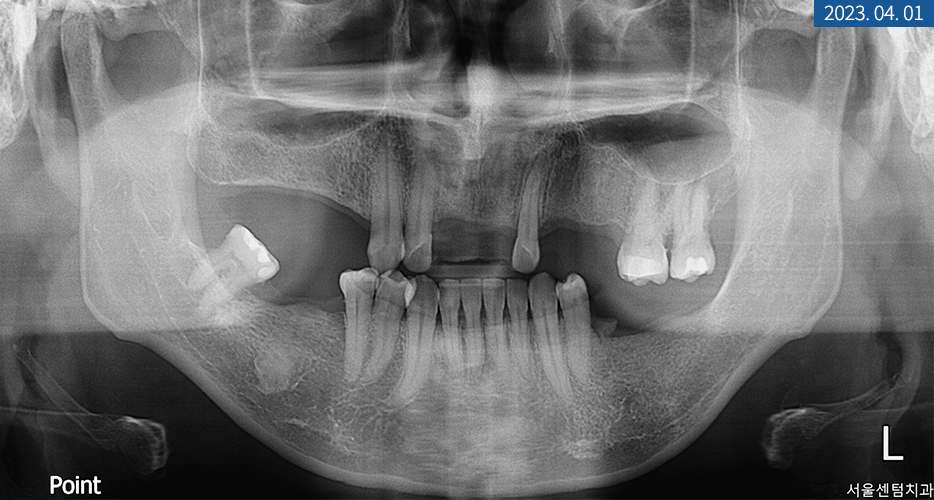

└ 첫 내원 당시 환자분의 잇몸과 치아 상태

위 사진의 상태를 갖고 계셨던

40대 남성분께서는 치아 상실이 돼서

저작 기능의 불편을 경험하고 계셨습니다.

파노라마 엑스레이를 찍어보니

상하악의 영구치가

전체적으로 많이 탈락돼있었습니다.

또한 좌측 상악 어금니에

치통과 더불어 염증 소견이 보여

신경 치료도 동반해야 했는데요.